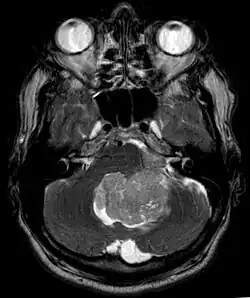

An ependymoma is a tumor that arises from the ependyma, a tissue of the central nervous system. Usually, in pediatric cases the location is intracranial, while in adults it is spinal. The common location of intracranial ependymomas is the floor of the fourth ventricle. Rarely, ependymomas can occur in the pelvic cavity.

Ependymomas make up about 5% of adult intracranial gliomas and up to 10% of childhood tumors of the central nervous system (CNS). Their occurrence seems to peak at age 5 years and then again at age 35. They develop from cells that line both the hollow cavities of the brain and the central canal containing the spinal cord, but they usually arise from the floor of the fourth ventricle, situated in the lower back portion of the brain, where they may produce headache, nausea and vomiting by obstructing the flow of cerebrospinal fluid. This obstruction may also cause hydrocephalus. They may also arise in the spinal cord, conus medullaris and supratentorial locations.[7] Other symptoms can include (but are not limited to): loss of appetite, difficulty sleeping, temporary inability to distinguish colors, uncontrollable twitching, seeing vertical or horizontal lines when in bright light, and temporary memory loss. It should be remembered that these symptoms also are prevalent in many other illnesses not associated with ependymoma.

Intracranial ependymomas, including supratentorial and posterior fossa, make up 90% of ependymomas in children. The supratentorial region is the upper brain region, or cerebrum, and contains the lateral and third ventricles. The posterior fossa, or infratentorial, is behind or below this region in the area of the brainstem and cerebellum and contains the fourth ventricle. A majority of intracranial pediatric ependymomas are in the posterior fossa.[15] Patients with intracranial ependymomas typically present with increased intracranial pressure that results in headaches, dizziness, nausea, and vomiting. The third location of ependymomas is within the central canal of the spinal cord. Spinal ependymomas comprise about 65% of adult ependymomas and most often occur in the lumbosacral region.[13] Patients with spinal ependymomas can present with back pain, numbness or weakness in the limbs, and urinary or bowel problems.